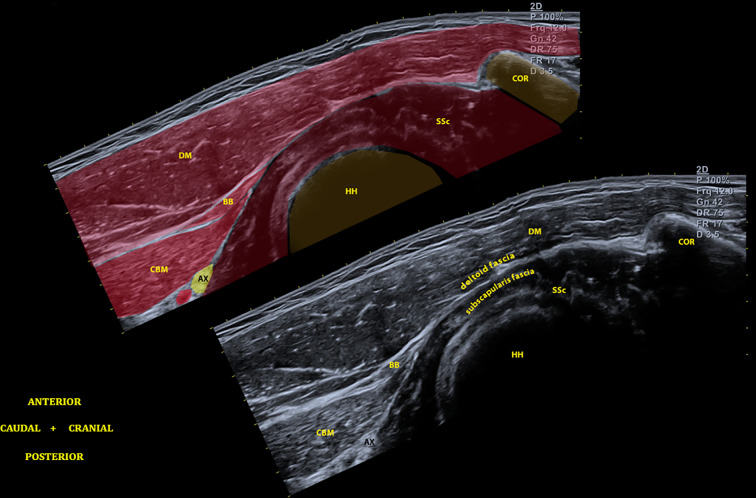

Description of the Procedures

For the SHAC block, with the patient in a beach-chair position and with the arm in extension, the subscapularis muscle is stretched posteriorly and becomes easily visible in the area below the deltoid fascia. With external rotation and abduction, the coracobrachialis and the biceps brachii muscles are displaced, allowing the visualization of the interfascial space between the deep lamina of the deltoid muscle fascia and the superficial lamina of the subscapularis fascia. The myotendinous nature of the lateral insertion of the subscapularis muscle produces a mixed echogenicity, with a characteristic dotted aspect that facilitates its localization in the US below the deltoid fascia (Fig. 1). Once the injection into the fascial space is achieved, we can proceed towards the glenohumeral pericapsular space by crossing the subscapularis muscle with the needle. By injecting the pericapsular space, we reach the terminal articular branches indistinctly from their origin. Furthermore, through the Weitbrecht foramen, a natural capsular foramen between the upper and middle glenohumeral ligaments, we also reach the intra-articular space (Fig. 2).

Fig. 1.

Panoramic view of the interfascial space between the deep layer of deltoid fascia and the superficial layer of the subscapularis fascia. HH humeral head, COR coracoid, SSc subscapularis, BB biceps brachii, CBM coracobrachialis, DM deltoid muscle, AX axillary nerve

Fig. 2.

SHAC block procedure. HH humeral head, COR coracoid, SSc subscapularis, BB biceps brachii, CBM coracobrachialis, DM deltoid muscle